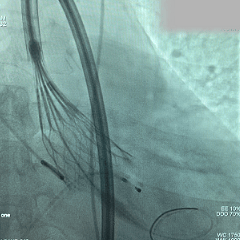

回收后再次释放

第二次展开造影,瓣膜位置尚可,基本无漏

多角度评估,瓣膜深度可

脱钩释放

脱钩后,瓣膜无位移

造影评估,瓣膜深度可,无瓣周漏